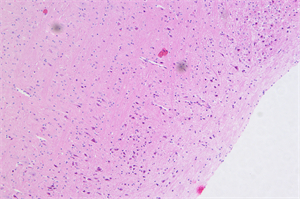

神经纤维系统研究对显微成像的清晰度、分辨率及荧光捕捉能力有着较高要求,近日,明慧工程师在了解到广州一研究所实验室需要适配神经纤维系统研究的显微镜与摄像头后,与实验室老师深入沟通,结合其科研需求与实际应用场景,推荐了NE910显微镜搭配MHD2000摄像头的显微解决方案,该方案因适配性强、贴合研究需求,快速获得了客户的初步认可。

为确保方案完全契合实验需求,工程师现场开展应用演示与实操指导。实践证明,该套解决方案在神经纤维系统荧光观察中表现出色:NE910显微镜采用NIS无限远光学系统,色彩还原度高,能清晰呈现神经纤维的细微结构,其灵活的荧光观察功能可有效减少背景信号干扰,贴合神经纤维研究的观测需求;搭配的MHD2000摄像头拥有2000万高像素,采用高灵敏度传感器,能精准捕捉荧光成像细节,助力研究人员高效记录实验数据。